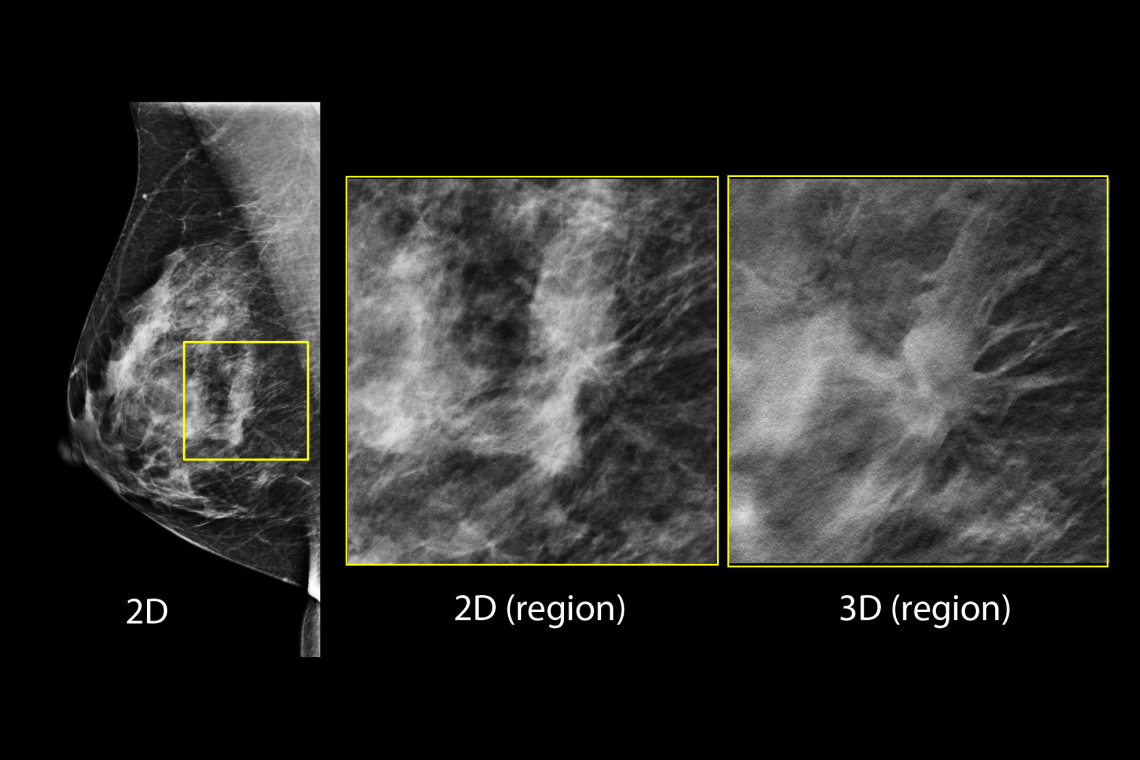

Hologic has further advanced breast cancer screening by producing 2D images from breast tomosynthesis data using C View software, resulting in a Low Dose Genius 3D Mammography exam with superior clinical performance compared with 2D alone.4

This Low Dose Genius 3D Mammography exam is performed in a rapid 3.7 second scan time for greater patient comfort and low patient dose, due to the elimination of 2D X ray exposures. The synthetic 2D images and 3D slices are reviewed together to make clinical decisions or diagnoses part of the Genius 3D Mammography screening exam.